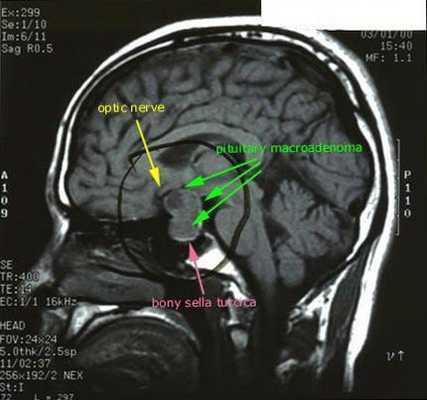

После подтверждённого гиперкортицизма необходимо проведение инструментальных методов исследования (МРТ гипофиза, КТ надпочечников).

При БИК в 80-85% случаев выявляют микроаденому гипофиза (опухоль до 10 мм), у остальных 15-20% — макроаденому (доброкачественное новообразование от 10 мм). [7]

- МРТ области турецкого седла с контрастированием

- МРТ области турецкого седла с контрастированием;

С помощью рентгенографии черепа (турецкого седла) выявляются макроаденомы гипофиза; при КТ и МРТ головного мозга с введением контраста - микроаденомы (в 50-75% случаев). При рентгенографии позвоночника обнаруживаются выраженные признаки остеопороза.